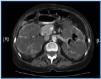

The case of a 70 year old woman is presented that was diagnosed with adult polycystic kidney disease, and that began long term haemodialysis four months earlier. Hospitalization was considered necessary due to the persistence of a constitutional syndrome, resistance to erythropoietin, anaemia, etc. In the anamnesis, the patient described the expulsion of air after urinating, without any other signs or symptoms. A urine culture grew E. coli. In an abdominal Computerised Axial Tomography (CAT) the presence of gas in the bladder and in the left urine collecting system is observed, which is frankly unusual (figure 1). Treatment was started with ciprofloxacin for 12 days and a urethral catheter was inserted, with complete clinical and radiological remission and a negative urine culture.

Figure 1.